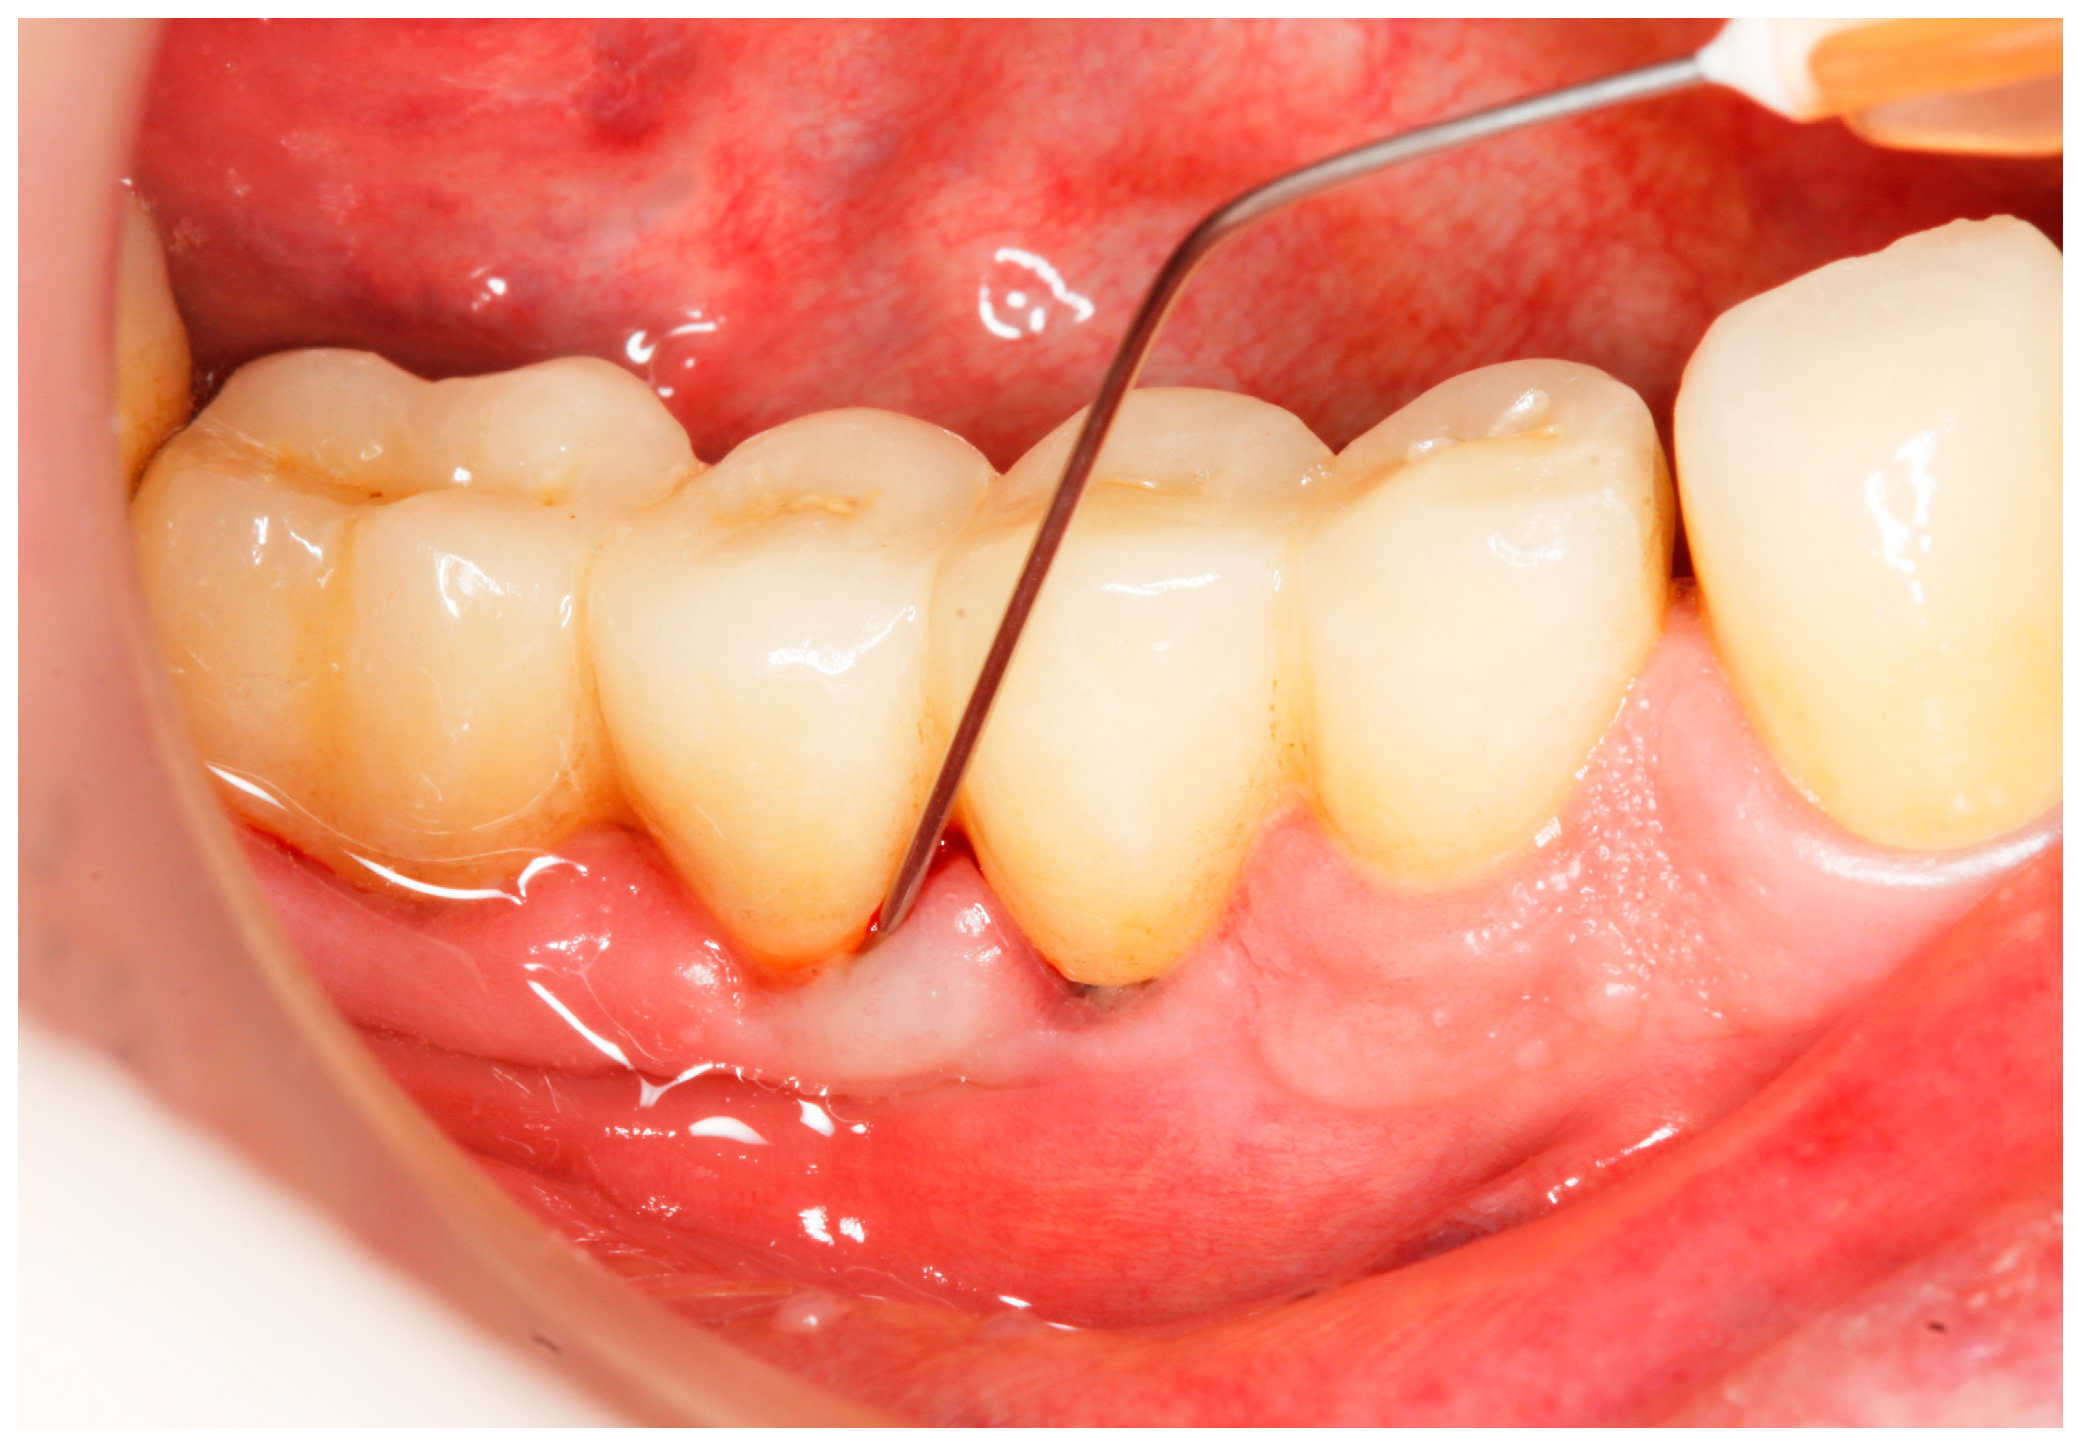

Baseline: Prior to PiM treatment, PMPR was performed in all subjects (Figure 3), for both teeth and implants. Each patient was assigned to one of the two treatment groups according to computer-generated randomization. One implant (the one with the greatest number of BoP points or the presence of a line of bleeding or profuse bleeding) with PiM in each patient was selected for the study. PMPR of the implants of interest was performed using an ultrasonic scaler with a plastic tip (Piezon® Master700 with Piezon® PI instrument, EMS, Nyon, Switzerland), and air polishing (Perioflow® handpiece, Airflow® PLUS powder, EMS, Nyon, Switzerland) was carried out at all sites. Piperacillin plus tazobactam gel Gelcide® (Italmed, Firenze, Italy) was prepared according to the manufacturer’s recommendations and was applied as follows: the solution was injected into the powder container, and the container was shaken until the solution became homogeneous. After mixing, the consistency of the mixture slightly increased, so it could be applied at the implant surface. Instrumentation was followed by subgingival application of the volatile mixture, depending on the patient’s group. For the Gelcide® group (test), topical application of Gelcide® was performed for the placebo group (control), topical application of a placebo (the volatile polymeric carrier alone) was carried out. The necessary quantity (not standardized) was then extracted from the mixed container with a syringe and inserted into the peri-implant sulcus at the apical extremity (Figure 4) until the excess became visible at the mucosal margin. Once the product had been applied, the excess was removed using a cotton ball.

Figure 4.

Application of Gelcide® in the peri-implant sulcus.